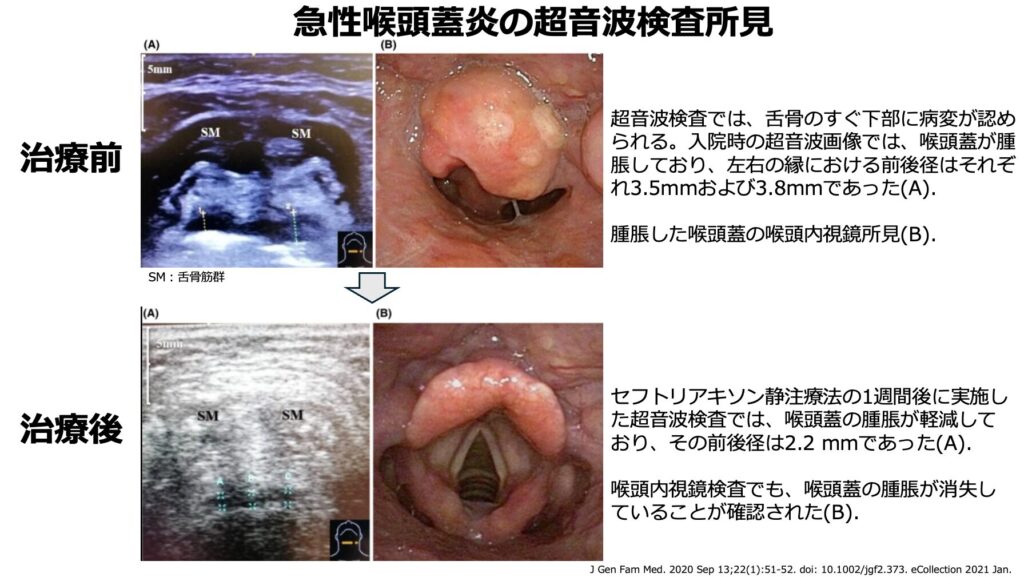

超音波検査

- 私自身試したことはありませんが、超音波検査でも喉頭蓋の腫脹が確認できるようです。